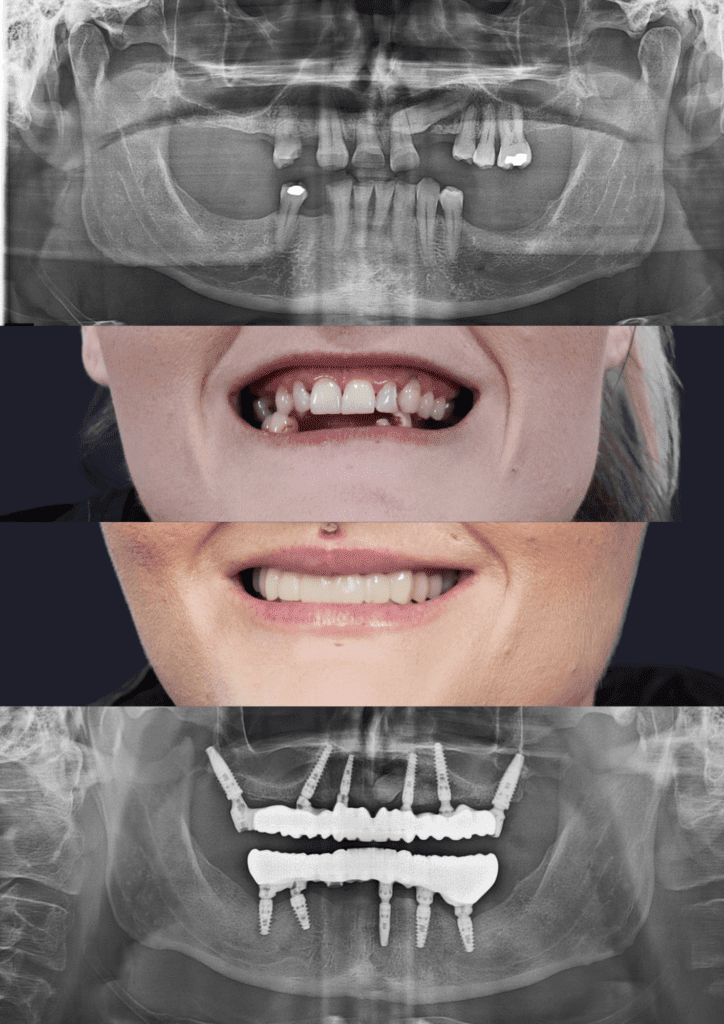

Before & After Treatment Gallery

The photos shown here document completed full-jaw implant treatments. Each case involved detailed planning, surgical placement of implants, and a custom-made fixed bridge. Treatment outcomes, timelines, and suitability vary and are assessed on a case-by-case basis.